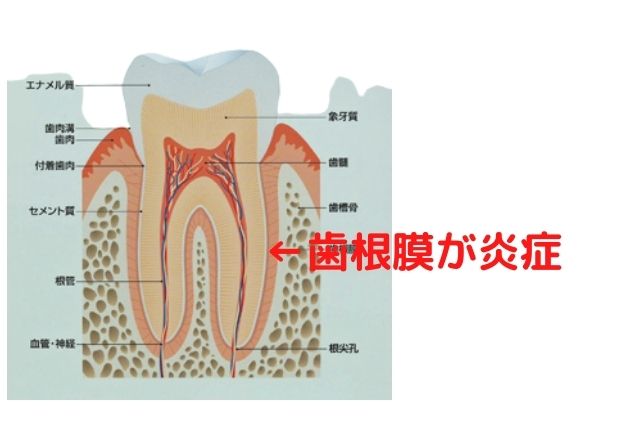

③歯周病が進行しやすくなる

銀歯の表面は傷がつきやすく、小さい傷に口の中の歯周病菌がくっつきやすくなります。

銀歯と歯茎の境目には歯周病菌他たくさんの菌がたまりやすい状態であり

銀歯を入れると歯周病の進行し悪化しやすくなります。